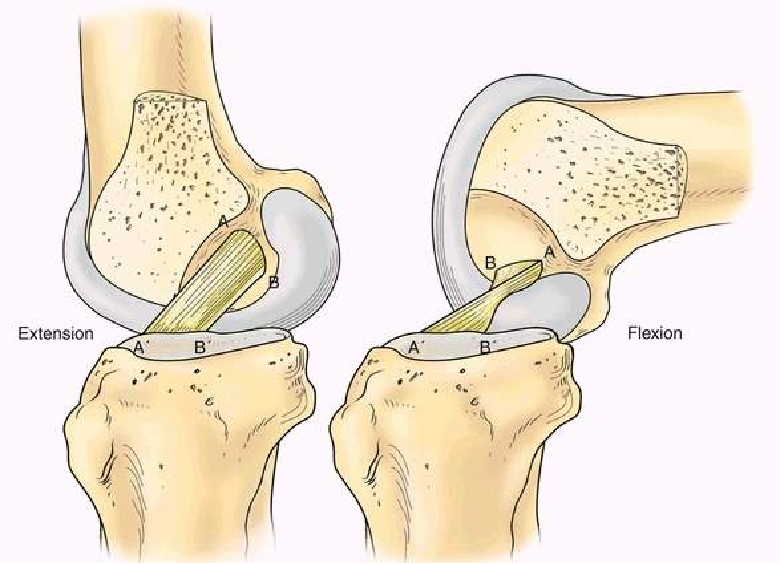

胎儿膝关节显示:两个功能束(AM,PL)

伸直时AM,PL的股骨点垂直排列,两束平行。

屈曲90°时,AM,PL的股骨点平行,两束交叉

膝关节屈曲90 °时PL松弛,而伸直时PL紧张状态